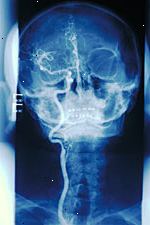

Μια αρτηριογραφία, που ονομάζεται επίσης ένας αγγειογραφία, είναι μια εικόνα ακτίνων Χ των αιμοφόρων αγγείων. Αυτό εκτελείται για να αξιολογήσουν διάφορες αγγειακές παθήσεις, όπως ένα ανεύρυσμα (αερόστατο ενός αιμοφόρου αγγείου), στένωση (στένωση των αιμοφόρων αγγείων), ή μπλοκαρίσματα.

Ένα εγκεφαλικό αρτηριογραφία αποτελεί αρτηριογραφία των αιμοφόρων αγγείων του εγκεφάλου.

Μια αρτηριόγραμμα περιλαμβάνει την εισαγωγή ενός αρτηριακού καθετήρα (ένα μακρύ λεπτό σωλήνα) σε ένα μεγάλο αιμοφόρο αγγείο και ενέσιμη σκιαγραφικό. Αυτή η χρωστική ουσία αντίθεσης προκαλεί τα αιμοφόρα αγγεία να εμφανίζονται αδιαφανή στην εικόνα ακτίνων-Χ. Αυτό επιτρέπει στο γιατρό να απεικονίσει καλύτερα τη δομή του δοχείου (ων) υπό εξέταση.

Για μια εγκεφαλική αρτηριογραφία, αρτηριακή πρόσβασης συνήθως λαμβάνεται στη μηριαία αρτηρία στη βουβωνική χώρα. Περιστασιακά, η βραχιόνια αρτηρία στο βραχίονα μπορεί να χρησιμοποιηθεί, και, σε πολύ σπάνιες περιπτώσεις, η καρωτιδική αρτηρία στο λαιμό μπορεί να χρειαστεί να χρησιμοποιηθούν. Η μηριαία αρτηρία είναι πιο συχνά χρησιμοποιείται επειδή είναι γενικά ευκολότερο να έχει πρόσβαση. Μόλις εισαχθεί ο καθετήρας, το σκιαγραφικό εγχέεται, και μια σειρά εικόνων ακτίνων Χ γίνεται. Αυτές οι εικόνες ακτίνων Χ δείχνουν την αρτηριακό, φλεβικό και κατασκευές σκαφών τριχοειδών του αίματος και της ροής του αίματος στον εγκέφαλο.

Εικόνα ενός αγγειογραφία της καρωτίδας

Καρωτιδική αγγειογραφία